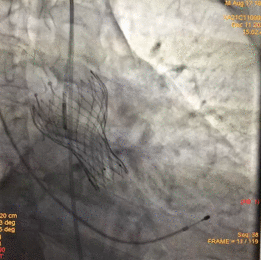

图片

根部造影

球囊预扩

释放瓣膜

瓣膜释放至2/3造影观察

瓣膜释放完毕

手术结果

术后造影及超声探查未见瓣周漏,跨瓣压差术前108mmHg,术后几乎无压差,术中及术后未出现相关并发症,手术圆满完成。